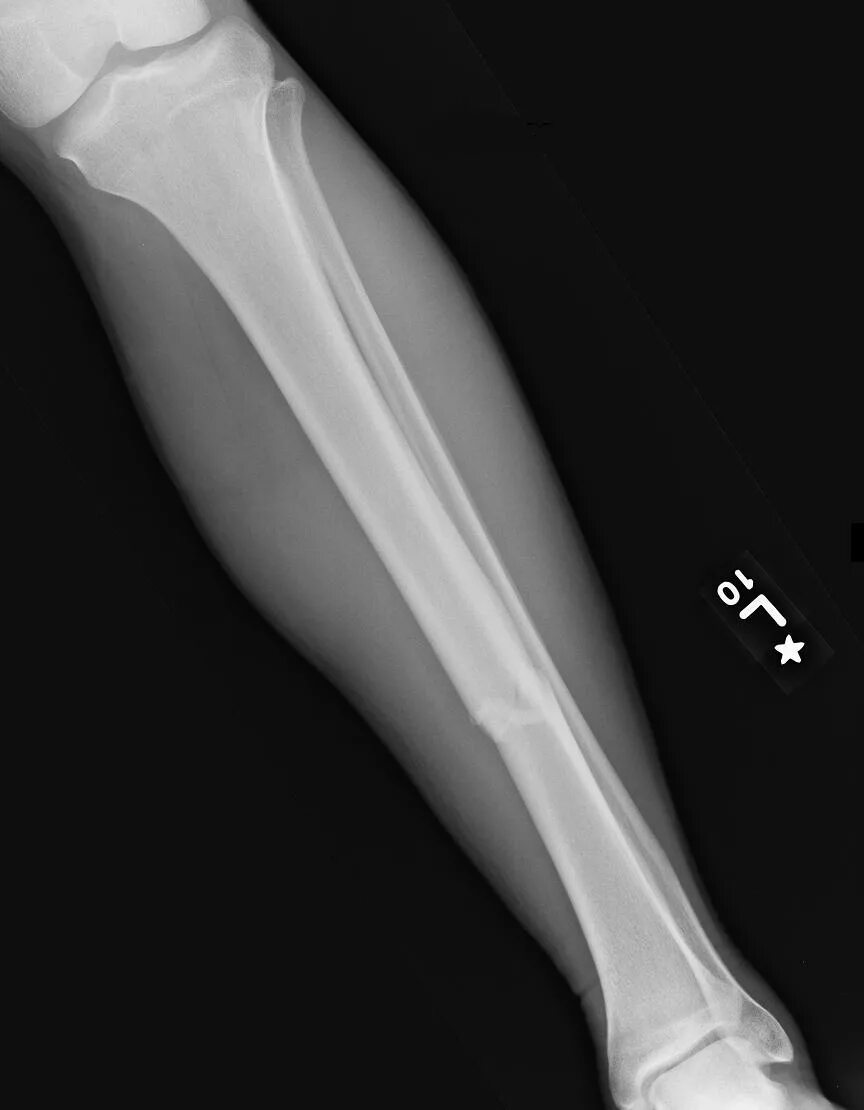

Curved tibia fibula